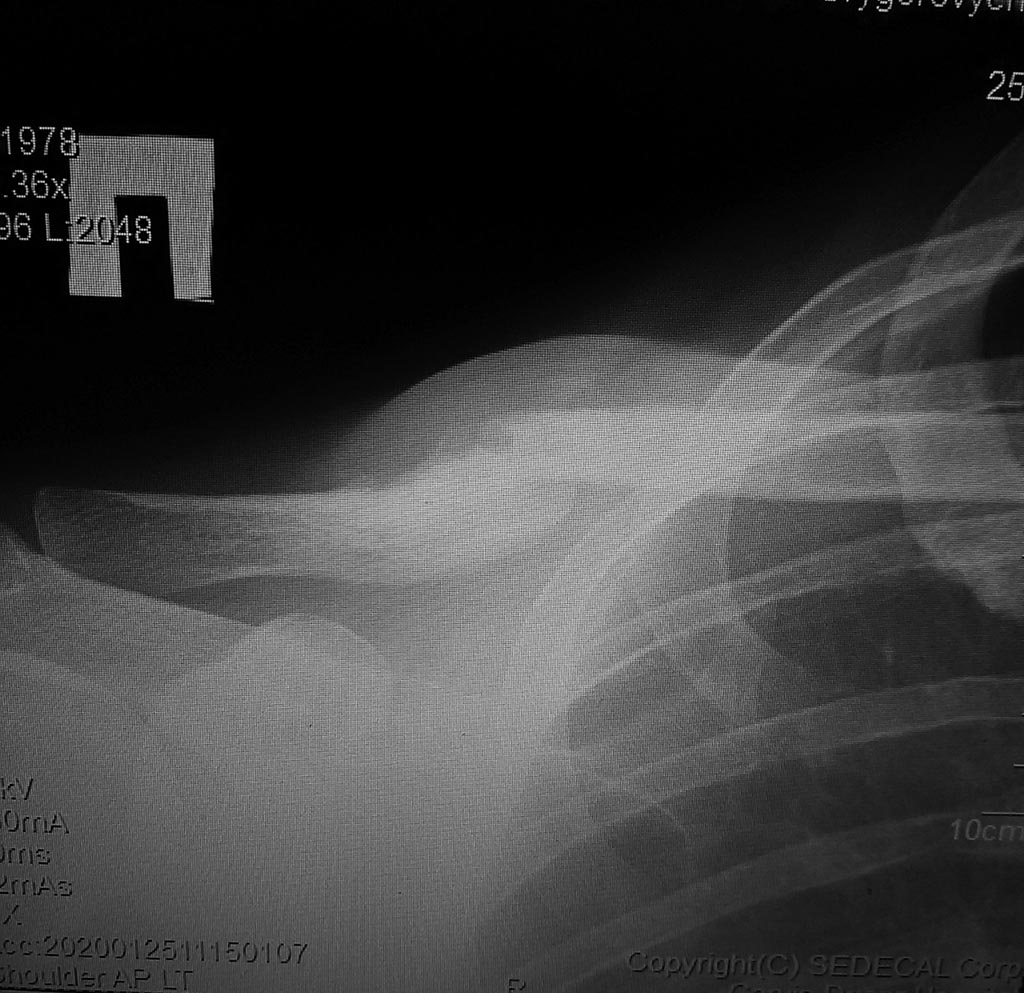

19.04.19 в результате падения получил закрытый косой перелом средней трети ключицы.

22.04.19 остеосинтез пластиной.Все шло хорошо. Через месяц вышел на работу. Через 1.5 снова сел на велосипед. Все шло хорошо к серидение лета уже работал топором на даче и кувалдой на работе. Место перелома никак не беспокоило. В ноябре/декабре даже в спорт зал пошел.

28.12.19 снял пластину.

02.01.20 сделал роковую ошибку. Пошел в тренажерный зал. Дал нагрузку... треснуло/хруснуло. Место перелома опухло болело. Хирург сказал все будет ок. Я ждал. Но не вытерпев сделал снимок. Фото которого я прилагаю. По своим , не медицинским, ощущениям сейчас так - часть ключицы от груди до места перелома поднялась и вышла вперед (и это видно невооруженным глазом она просто торчит аномально под кожей) а часть от перелома до лопатки ушла вниз и во внутрь. Хирург по снимку сказал что срастется и все будет норм.

Хотелось бы узнать ваше мнение. Можно ли так оставить.